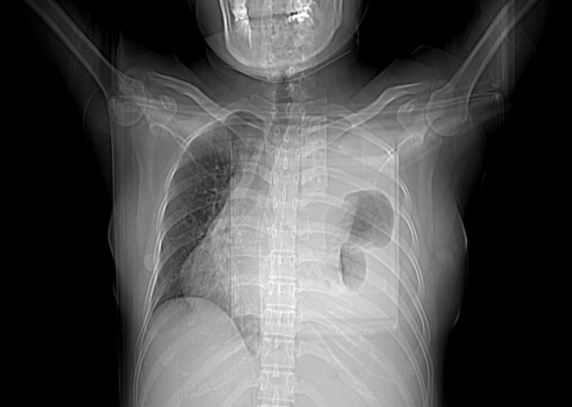

患者28岁女性,胸闷气促伴咳嗽、盗汗5天,加重1天。

患者5天前情绪激动后出现胸闷气促,伴咳嗽、盗汗,为干咳,感畏寒,无发热,无全身肌肉酸痛,无恶心呕吐,无头痛头晕,遂至当地诊所就诊,予输液(具体药物不详)及口服阿莫西林、头孢药物治疗后,自诉无明显好转。今患者感胸闷气促加重,仍有咳嗽、盗汗,咳少许痰,痰中带血丝,无胸痛心悸,无黑矇晕厥,至我院急诊,查血常规+SCRP 白细胞 12.30×109/L↑,中性粒细胞百分数 76.9%↑,淋巴细胞百分数 15.2%↓,高敏C反应蛋白 21.34mg/L↑;心超提示心包积液,胸腔积液B超示双侧胸腔积液,请我科会诊后,拟“心包积液、胸腔积液”收住入院。

2021-03-13 我院心脏超声示心包积液。胸部超声示双侧胸腔积液。腹部超声示腹腔未见明显积液。胸部平扫(CT)提示前纵隔占位性病变,左侧心膈角区淋巴结;左侧大量胸腔积液,右侧少量胸腔积液,左肺局部膨胀不全,右肺中叶小结节,纵隔略右偏,心包大量积液。

1、多浆膜腔积液(病因待查)

2、纵隔肿物

3、肺结节